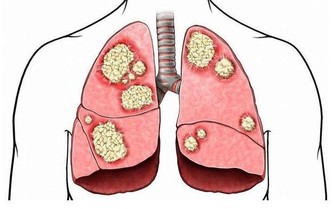

1抵抗癌細胞有相關的實驗證明,用黃芩泡水喝會對體內的癌細胞起到抵抗作用,這就是因為黃芩里含有的黃芩黃酮成分起到的作用。